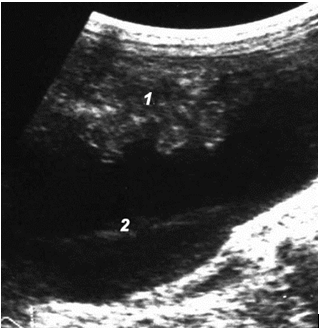

При «среднем» гемоперитонеуме, помимо малого таза, кровь эхографически определяется в печеночно-почечном кармане, латеральных каналах, периспленическом пространстве, ее объем колеблется от 7,6 до 25,8 мл/кг массы тела (рис. 12).

Рис. 12. «Средний» гемоперитонеум: 1 – печень; 2 – почка; 3 – кровь.